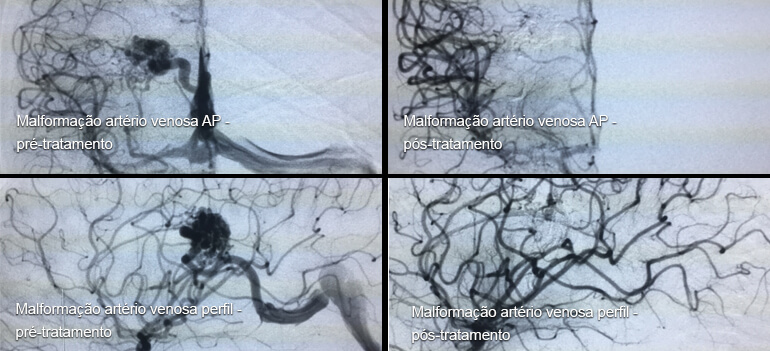

Malformação artério-venosa/fistula dural intracraniana e medular

As malformações vasculares são patologias raras que se caracterizam pela comunicação anômala entre artérias e veias (fístula) , nutridas por artérias intracranianas, medulares ou durais, com drenagem venosa precoce.

Modernamente, a conduta terapêutica nesses pacientes deve ser multidisciplinar, considerando-se as possibilidades dos tratamentos endovascular, cirúrgico e radioterápico. Os tratamentos propostos dependem da localização, das dimensões e das características de nutrição e drenagem da malformação.